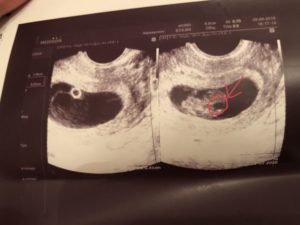

Для диагностики гипертонуса используется ультразвуковое исследование, при проведении которого может быть выявлен гипертонус задней стенки матки, а также передней. Однако, этот признак не всегда может говорить об угрозе прерывание беременности. Матка может прийти в тонус в ответ на прохождение ультразвуковой волны через ее стенку.

Также на ультразвуковом исследовании при выполнении цервикометрии (измерение длины шейки матки) диагностируется истмико-цервикальная недостаточность (укорочение шейки матки, открытие ее внутреннего зева).